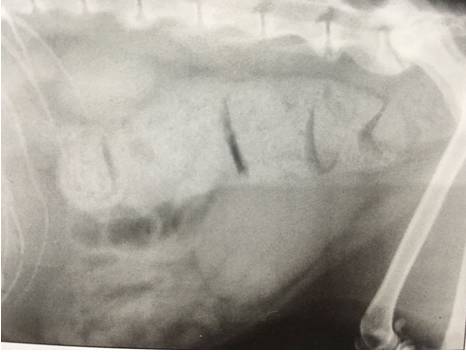

(一例便秘:腹部X线检查图为结肠积粪)